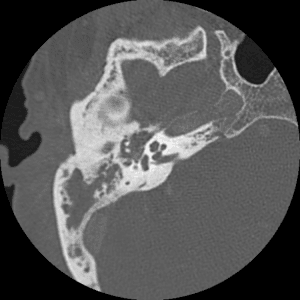

Temporal Bone

Resident/fellow-level anatomy